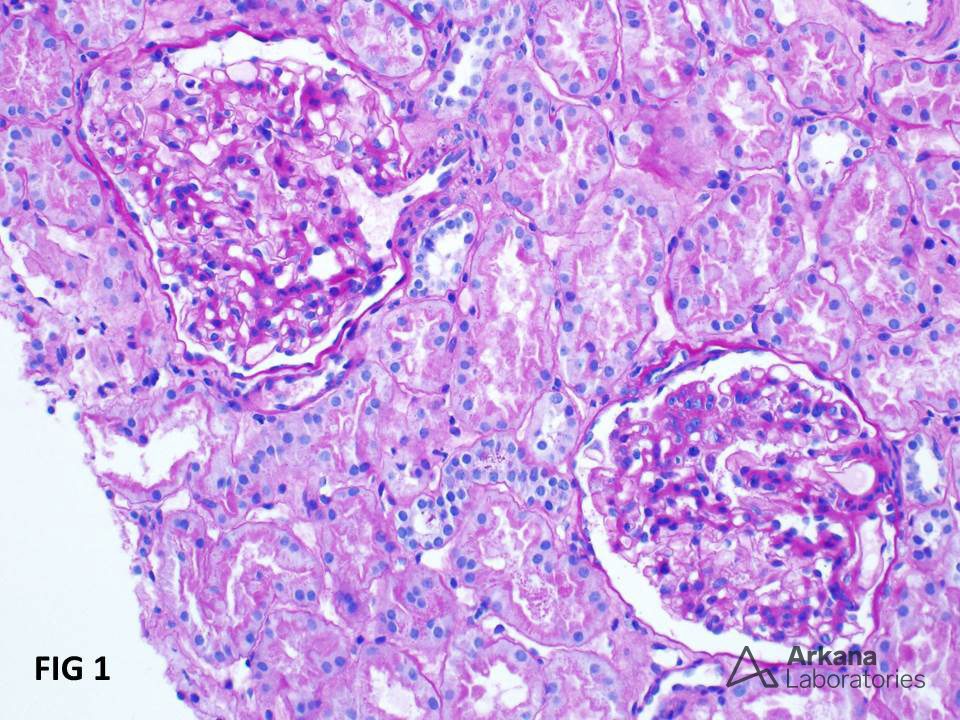

Hematúria e Proteinúria: quando o erro se repete…A glomerulonefrite por C3 (GNC3) resulta de ativação descontrolada da via alternativa do complemento e pode simular uma GN pós-infecciosa. O diagnóstico correto depende do reconhecimento do padrão de deposição de C3 e da investigação genética. Com terapias-alvo como o eculizumabe e o iptacopan, identificar precocemente a GNC3 pode mudar o desfecho do paciente.